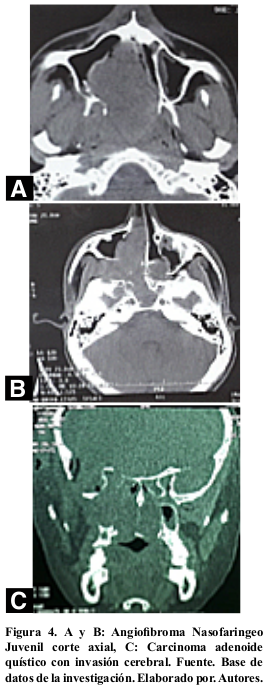

El estudio histopatológico reportó tumores benignos en el 72,41% (21; 29) de los casos, siendo el más frecuente el AFNJ 68,97% (20; 29), tumores cerebrales invasivos 6,90% (2; 29) (Figura 4 y 5); seguido de los tumores malignos con el 20,69% (6; 29) siendo el carcinoma adenoideo quístico el más frecuente. Tabla 1 y 2.

Los tumores malignos presentaron una frecuencia menor; los reportes de patología fluctuaron entre un 27,0%14 a 34,0%15; comparado con el 20,69% de este estudio; siendo las estirpes encontradas el carcinoma adenoide quístico, nasofaríngeo y sarcoma lo que concordó con la literatura29, sin embargo hay tumores menos frecuentes como adenocarcinoma, condrosarcoma y linfomas. El sitio de inicio de estos tumores fue el seno maxilar en el 53,0% de casos28, en la casuística se evidenció en el 34,0%.